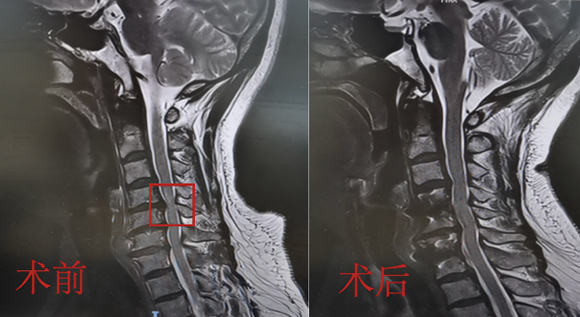

脊柱脊髓神經(jīng)微創(chuàng)中心以微創(chuàng)技術(shù)為引領(lǐng),以功能恢復(fù)為目標(biāo),主要治療脊柱外傷、腫瘤、退行性病變、脊柱畸形等疾病。團(tuán)隊(duì)利用神經(jīng)外科顯微技術(shù),結(jié)合神經(jīng)內(nèi)鏡微創(chuàng)技術(shù),對(duì)脊柱間盤變性疾病、頸腰椎管狹窄、頸腰椎間孔狹窄、頸腰椎間盤突出、頸腰椎體不穩(wěn)、脊柱骨折、寰樞椎脫位、脊柱腫瘤、椎管內(nèi)腫瘤、脊髓損傷、脊髓空洞、脊髓栓系等疾病進(jìn)行高效、特色手術(shù)治療,如顱頸交界區(qū)畸形寰枕減壓內(nèi)固定術(shù)、脊柱腫瘤全脊椎切除內(nèi)固定術(shù)、微創(chuàng)椎管內(nèi)腫瘤切除術(shù)、微創(chuàng)脊柱旁腫瘤切除術(shù)、寰樞椎脫位椎間融合內(nèi)固定術(shù)、脊柱骨折微創(chuàng)經(jīng)皮椎弓根釘內(nèi)固定術(shù)、經(jīng)椎間孔椎間融合內(nèi)固定術(shù)(MIS—TLIF)等,最大程度降低脊柱脊髓手術(shù)創(chuàng)傷,具有創(chuàng)傷小、輸血少、恢復(fù)快、口碑好,出院早等優(yōu)勢(shì)。